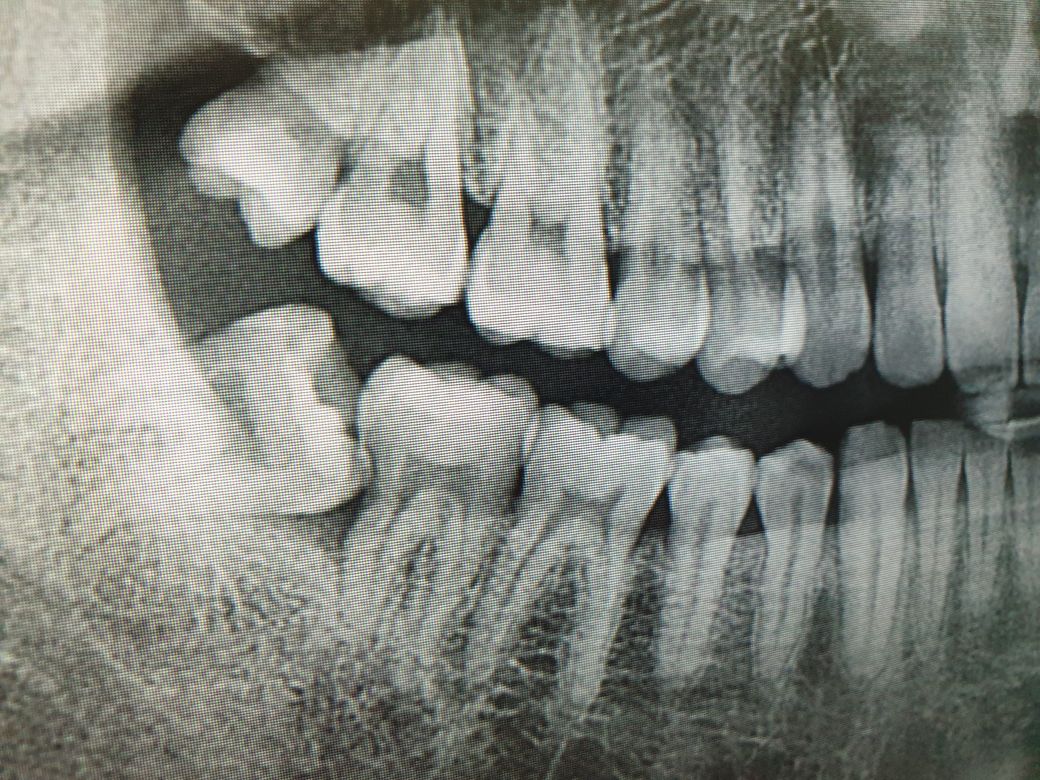

파노라마? 그사진을 찍었는데 사랑니 머리쪽 조금이 어금니에 붙어잇는상태로 잇몸에 묻혀있다고하더라구요

이상태인데. 안쪽에 음식물도 끼고 이쑤시개로 빼네는게 한계가있더라구요 많이아플까요?

• 1번 째 사진

방사선 사진으로 보았을 때 부분 매복 사랑니로 보입니다. 위치나 형태로 보아 뽑기 힘들지 않아 보이며 5~10분이내에 발치 할 수 있습니다. 하지만 정확한 위치를 파악하기 위해 Dental CT를 찍을 것이고 그러면 훨씬 발치하는데 통증과 부작용을 줄이고 뽑을 수 있습니다. 지금 상황으로 보아 앞쪽 어금니 뒷 부분에 충치를 발생시키고 잇기 때문에 빨리 뽑는것이 좋습니다.

사진으로 볼 때 치아가 기울어져있어서 양치질이 쉽지 않을 것으로 보입니다.

이런경우 치아윗부분을 조각내어 발치해야합니다.

2등분해야할 수 도 있고, 3,4등분 해야할 수 도 있습니다.

마취만 잘 된다면, 크게 아프진 않습니다. 다만, 마취가 풀린뒤 통증이 며칠 있을 가능성이 높습니다.